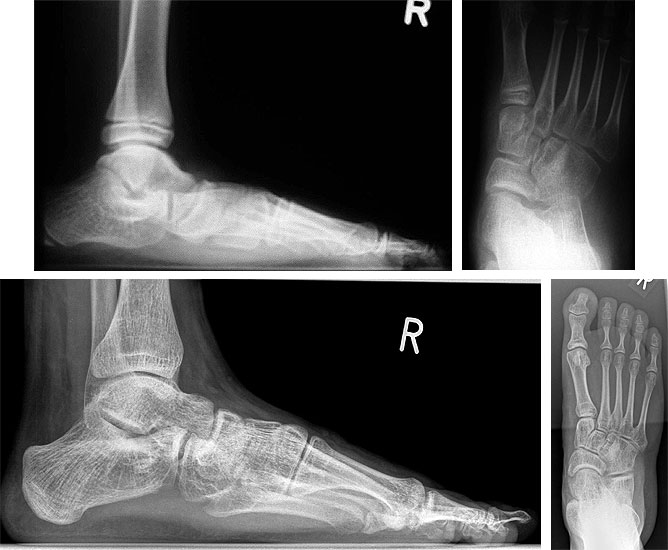

Isolierte subtalare Arthrodese bei TC-Coalitio

Die isolierte talocalcaneare Arthrodese stellt bei nichtresektabler symptomatischer Coalitio oder bei längerfristig persistierenden Beschwerden nach Resektion im Jugendlichenalter wie beim Erwachsenen 11 eine funktionell sehr befriedigende Lösung dar (Abb. 5 und 6), zumal bereits eine weitgehende Einsteifung durch die Coalitio vorbestehend ist. Sie kann – wie die Resektion – von einem medialen Zugang aus als in-situ-Arthrodese durchgeführt werden (auch eine intraoperative Entscheidung Resektion versus Arthrodese ist möglich). Bei deutlicher Rückfuß-Valgus-Deformität oder der Notwendigkeit der Interposition von corticospongiösen Spänen ist ein Zugehen von lateral (auch als Grice-Arthrodese (Grice 1952)) oder auch von dorsal in Bauchlage mit und ohne Resektion der Coalitio alternativ möglich. Auch Kombinationen mit tarsalen Osteotomien zur Korrektur weiterer Fehlstellungskomponenten kommen entsprechend dem oben beschriebenen Vorgehen bei Coalitio-Resektion in Betracht (Abb. 6).

Die auch in neuerer Zeit noch standardmäßig empfohlene Triple-Arthrodese 8 sollte Fällen mit sekundären talonavicularen Veränderungen vorbehalten bleiben. In den meisten Fällen ist jedoch die Chopart-Gelenklinie bei talocalcanearer Coalitio noch erhaltungswürdig; das „talar beaking“ sollte nicht mit einem Osteophyten verwechselt und als Hinweis auf höhergradige degenerative Schädigung des Talonavicular-Gelenkes verkannt werden.

Operatives Vorgehen: Zunächst ist die Frage zu entscheiden, ob die Coalitio reseziert oder belassen werden sollte. Bei breiter, kompletter Coalitio ohne Deformität kann eine in-situ-Arthrodese von anterolateral über einen Sinus-tarsi-Zugang durchgeführt werden. Ein corticospongiöser Span wird zur Verblockung paßgenau in ein ensprechend ausgefrästes oder ausgesägtes Fenster im lateralen Subtalargelenk eingebolzt. Alternativ kann auch ein Knochenspan extraartikulär in den Sinus-tarsi eingepaßt werden, entsprechend der Grice-Arthrodese. Bei inkompletter, schmerzauslösender Coalition erscheint die Resektion von medial aus sicherer. Das verbleibende Subtalargelenk (hintere Kammer) wird danach mit dem Hintermann-Distraktor aufgespreizt und mit Küretten und Knochenfräse entknorpelt und subchondral angefrischt. Eine leichte Rückfuß-Valgus-Deformität kann hierbei gut mit ausgeglichen werden; das bei der Coalitio-Resektion angefallene knöcherne Material kann als Spongiosaplastik Verwendung finden, eine zusätzliche Spongiosa-Entnahme ist fakultativ möglich und nicht selten sinnvoll. Die Osteosynthese erfolgt bei geschlossener Tuber-Wachstumsfuge mit zwei perkutan unter BV-Kontrolle eingebrachten Lochschrauben mit Kompressionseffekt, bei offener Fuge mit zwei K-Drähten der Stärke 1,6 mm.

Bei höhergradiger Planovalgus-Deformität kann mit corticospongiösen Spänen von lateral aus gearbeitet werden; alternativ ist eine Korrektur auch über eine zusätzliche Tuber-Osteotomie möglich. Verbleibende Mittel-Vorfuß-Deformitäten (Abduktion, Supination) sollten wie oben beschrieben zusätzlich durch Calcaneus-Verlängerungs-Osteotomie bzw. Cuneiforme-mediale-Osteotomie behoben werden.